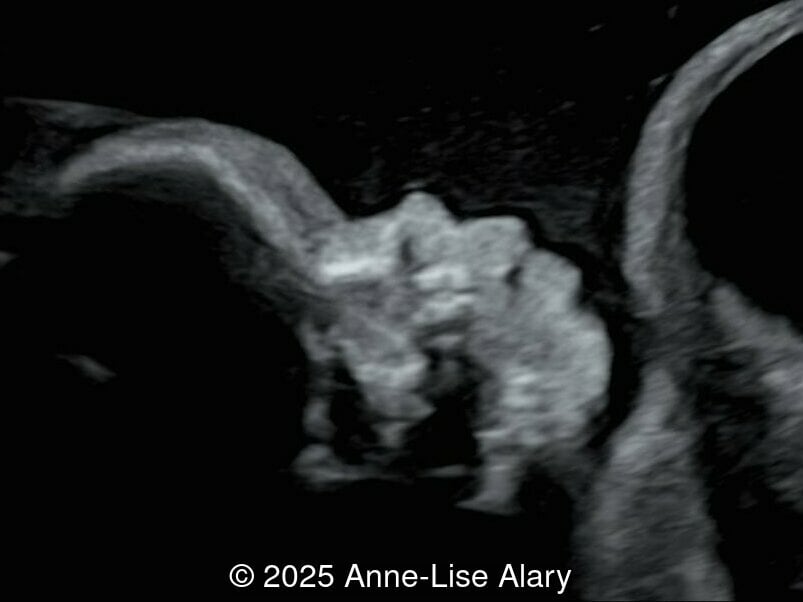

Image 2

Axial image of the abdomen

Our prenatal ultrasound revealed a male fetus with megabladder, dilation of both ureter and kidneys, and thinned kidney parenchyma consistent with Lower Urinary Tract Obstruction (LUTO).  Additional findings suspected on ultrasound and confirmed on computed tomography included: